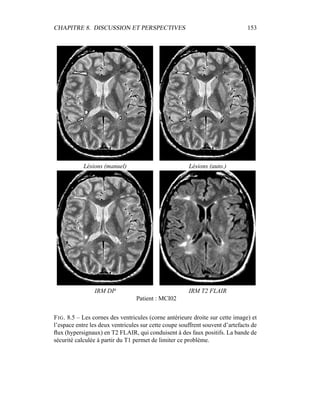

tons, auxquelles le masque binaire du cerveau a été appliqué – et fournit en sortie

3 labélisations : matière blanche, matière grise, LCR. Comme indiqué dans les

CHAPITRE 4. SEGMENTATION EN TISSUS 53

équations 4.10 et 4.11, l’algorithme EM donne deux grands résultats :

– la labélisation des segmentations via les γk

i